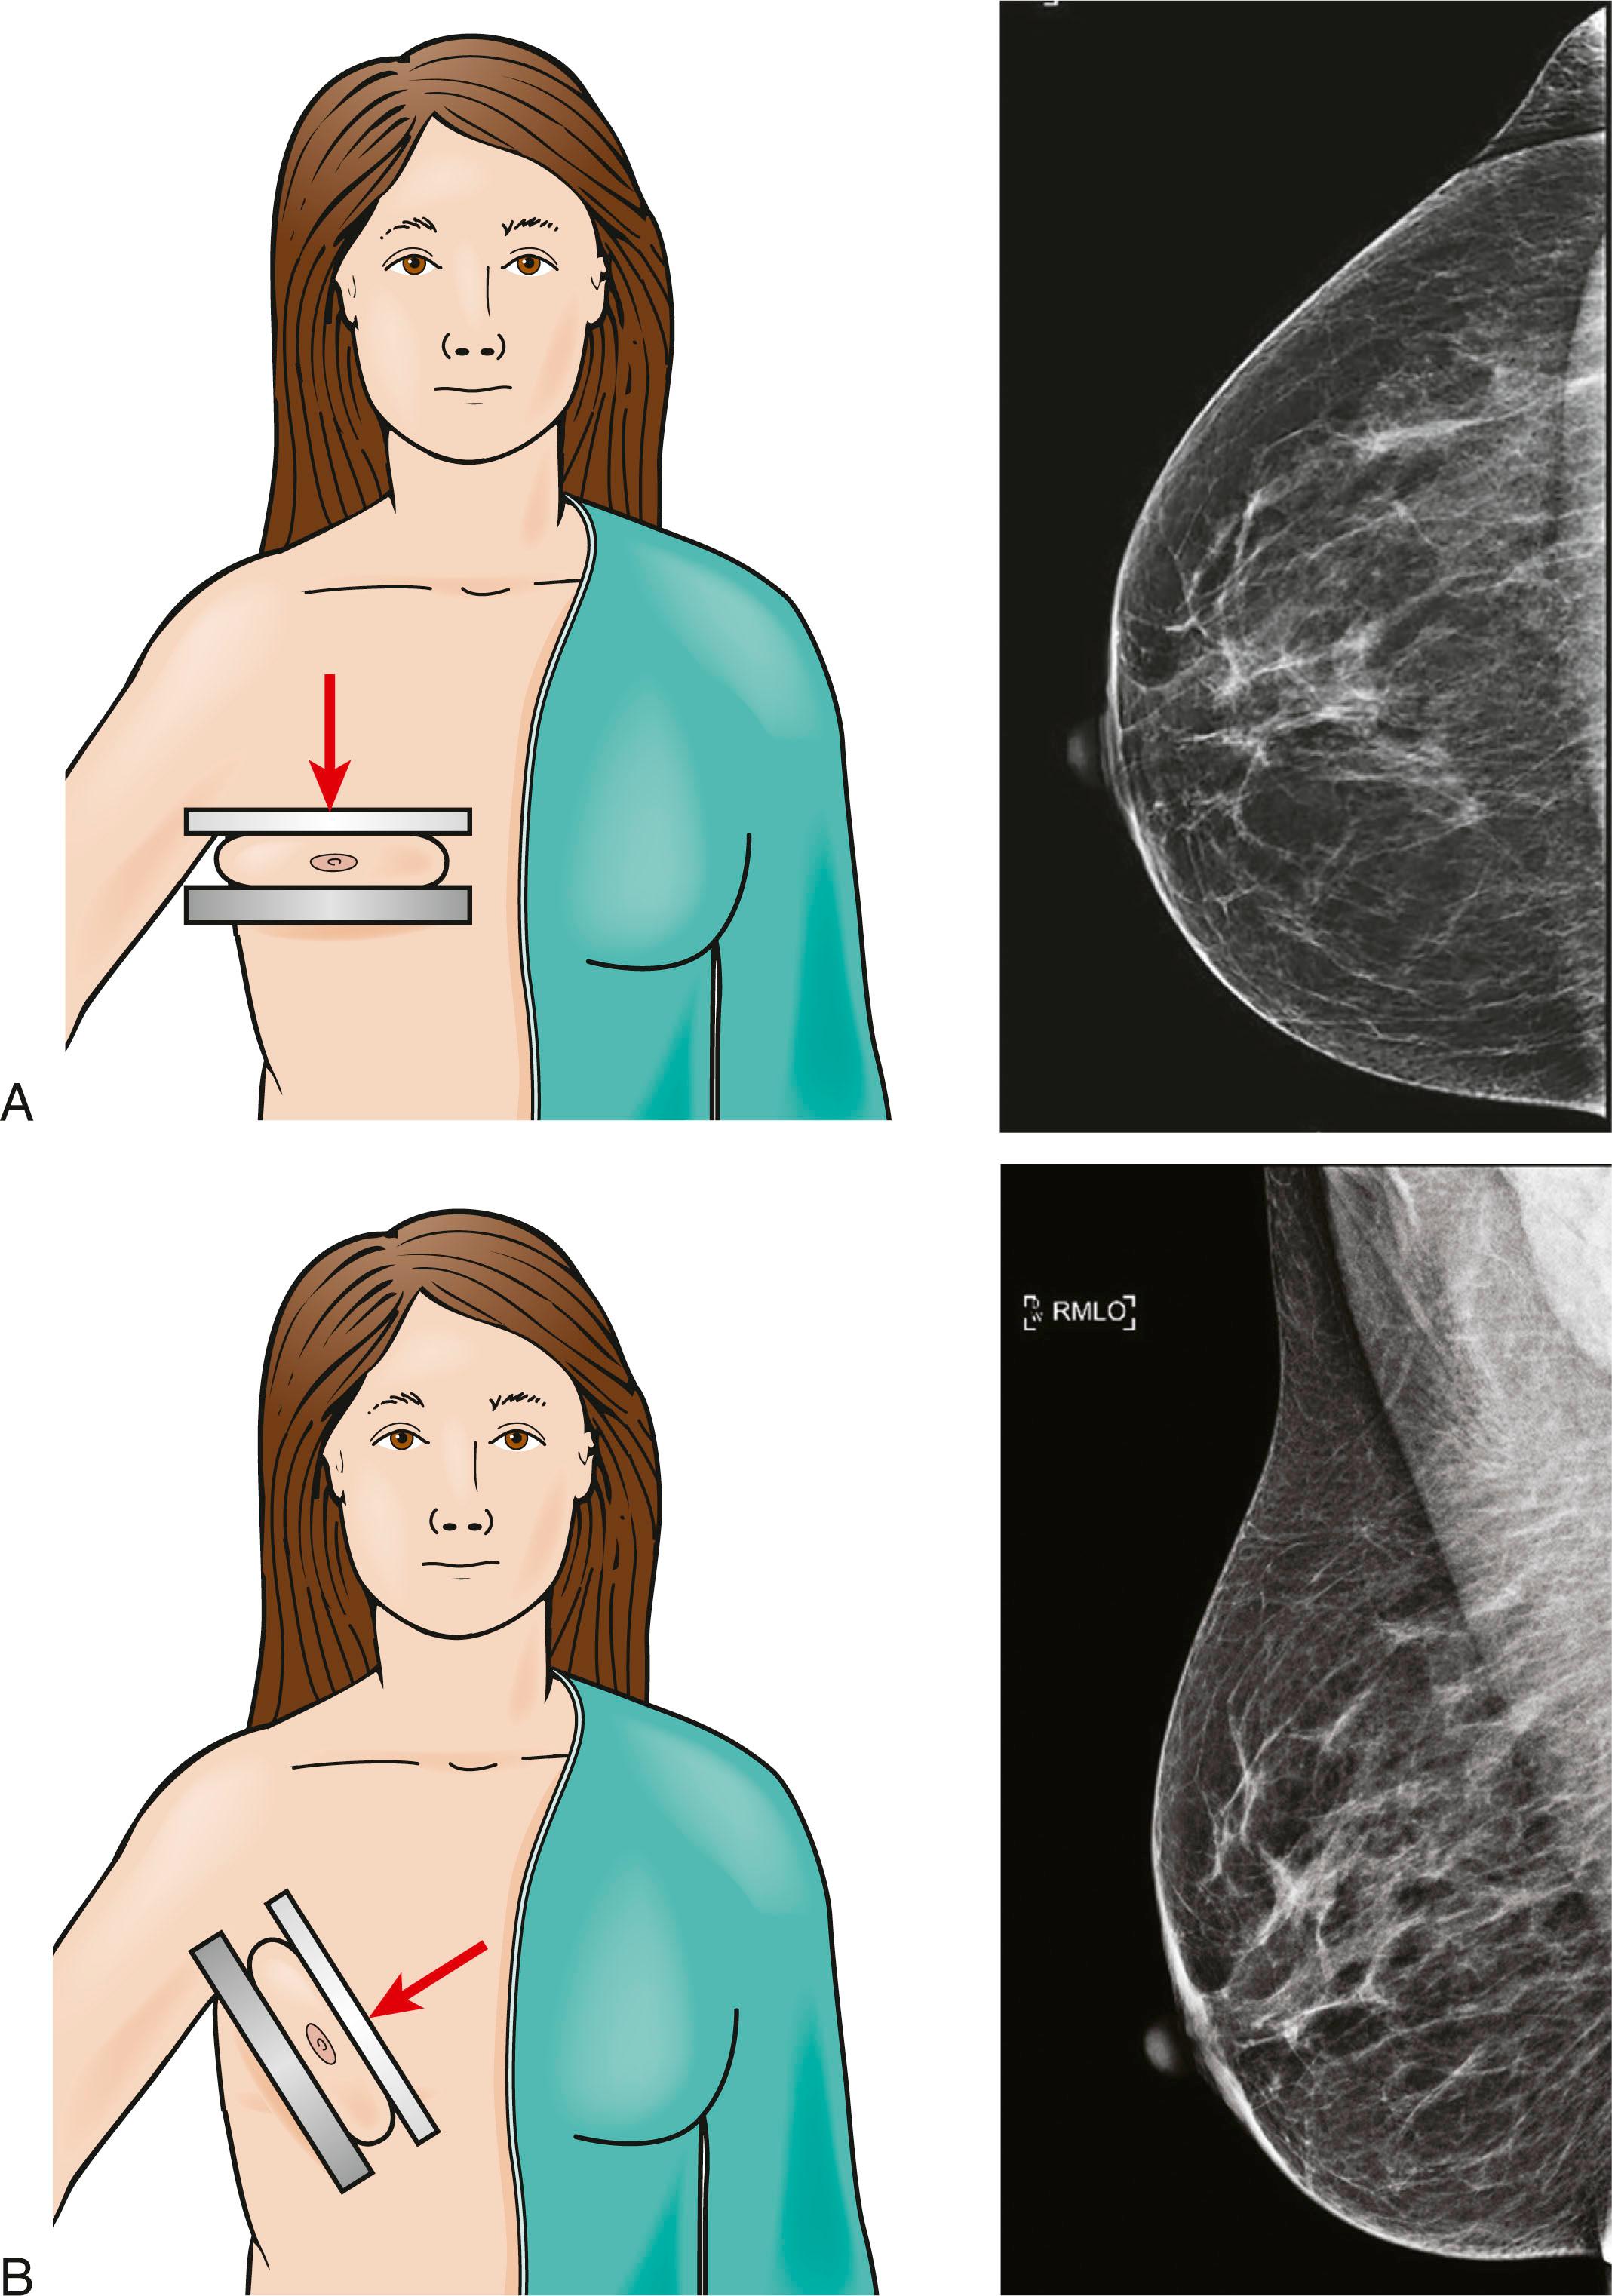

Principles of Mammography

Mammography is a dedicated imaging modality that uses low-energy x-rays to obtain two standardized views of each breast for the purpose of breast cancer screening: mediolateral oblique (MLO) and cranio-caudal (CC). The breast is positioned and stabilized between compression parallel plate paddles in order to prevent motion blurring, to minimize radiation dose, and spread overlapping tissues ( Fig. 12.1 ).

Fig. 12.1, (A) Acquisition of cranio-caudal, and (B) mediolateral oblique views of the right breast.